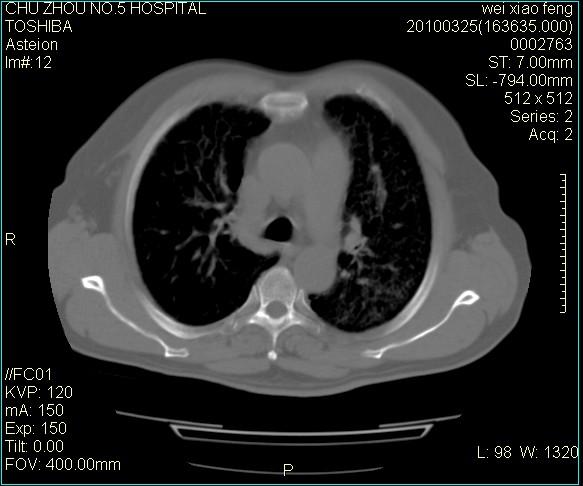

男,60岁,反复咳、痰、喘3月,加重3天。

双肺间质性改变。

考虑双肺血型潘散肺结核/

间质性肺炎伴间质纤维化!不排除伴有职业病!

双肺间质纤维化,双肺血型潘散肺结核。

考虑间质性肺炎伴间质纤维化。

右肺中叶结节影为原发灶,考虑右肺中叶周围型肺癌并淋巴道转移